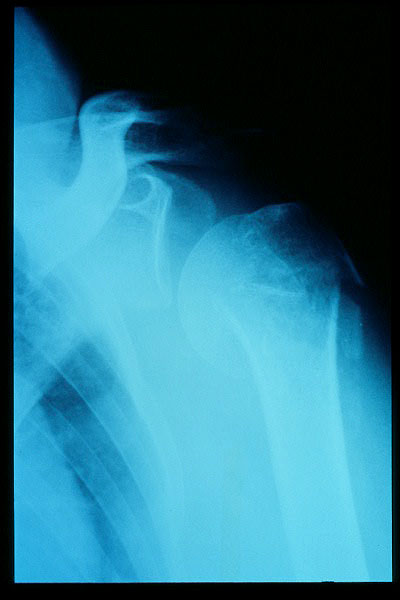

APR Luxación de hombro